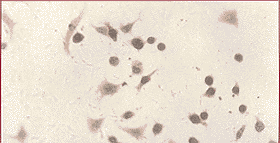

2.2 外源性p16基因在CNE-2的表达情况:免疫组织化学检测结果显示CNE-2-p16细胞p16蛋白阳性,表明外源性p16基因已经整合入CNE-2细胞并表达,而CNE-2-vect组及对照组CNE-2细胞,p16的检测均阴性(见图1、图2)。

图1 CNE-2-p16细胞p16蛋白免疫组化染色阳性结果,可见细胞核呈明显的黄褐色,同时胞浆也出现黄褐色,但明显弱于细胞核(×400)

图2 CNE-2,CNE-2-vect细胞p16蛋白免疫组化染色服用性结果,细胞核及细胞浆均呈蓝色(×200)